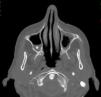

Si bien existen otros cambios estructurales asociados a la migraña, la complicación más importante de esta patología tal vez sea el infarto migrañoso3. En estos casos, los pacientes suelen presentar intensas crisis migrañosas acompañadas de otros síntomas, como aura y déficit neurológico focal, habitualmente sin secuela funcional. Es común en mujeres migrañosas menores de 45 años y con factores de riesgo cardiovascular. En imágenes, el área afectada muestra una pequeña lesión, generalmente menor de 3cm, con características de infarto, muchas veces silente (fig. 2).